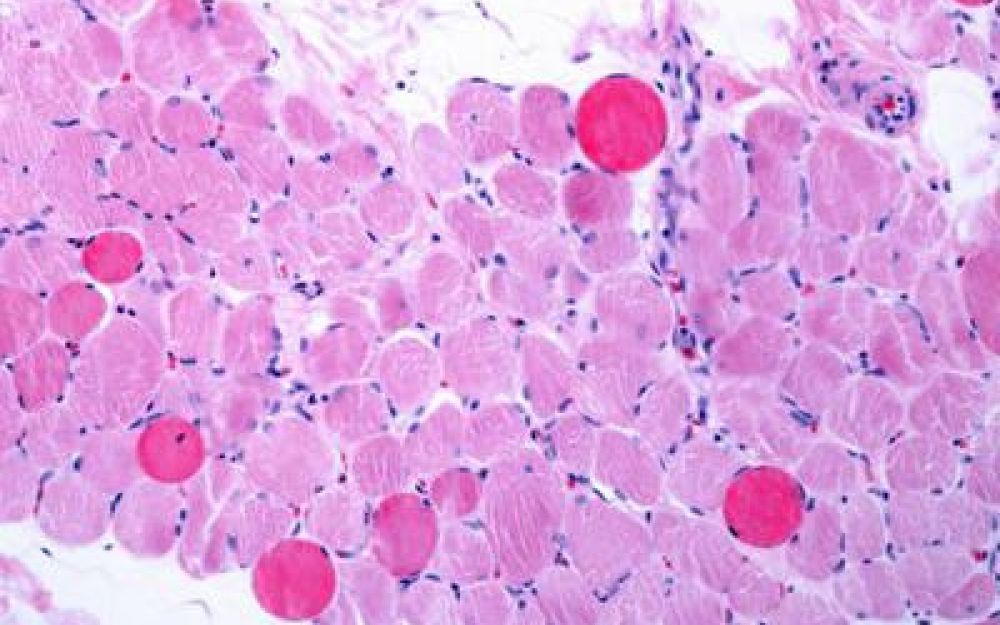

Roma, 4 nov. (Adnkronos Salute) – Sono positivi i risultati di un’analisi dei dati a lungo termine – comprese le prime valutazioni dello studio multicentrico in aperto Guardian, attualmente in corso – che valuta Agamree* (vamorolone) in pazienti affetti da distrofia muscolare di Duchenne (Dmd). Lo annuncia in una nota Santhera Pharmaceuticals, precisando che l’analisi ha incluso pazienti mai trattati con corticosteroidi e che hanno iniziato il trattamento con Agamree tra i 4 e i 7 anni di età nell’ambito di studi clinici, proseguendo poi attraverso vari programmi di accesso tra cui lo studio Guardian.

Sono stati analizzati i dati di un massimo di 110 pazienti, con un numero variabile in base alla disponibilità delle informazioni. In questa analisi i pazienti avevano ricevuto il trattamento per un massimo di 8 anni, con un follow-up mediano di circa 5 anni. La maggior parte dei pazienti ha mantenuto dosi elevate (4-6 mg/kg/giorno) in contesti clinici di real world durante il periodo di osservazione. I risultati mostrano che i pazienti trattati con vamorolone hanno mantenuto la funzione motoria durante il follow-up prolungato, dimostrando un’efficacia duratura del trattamento misurata in base al tempo di perdita della deambulazione paragonabile a quella dei corticosteroidi standard (p=0,91). Nelle analisi di sottogruppi prestabilite non sono state osservate differenze rispetto al deflazacort o al prednisone assunti quotidianamente. I dati – riporta l’azienda – continuano a confermare un profilo di sicurezza e tollerabilità differenziato rispetto ai corticosteroidi tradizionali. I pazienti trattati con Agamree hanno registrato un tasso significativamente inferiore di fratture vertebrali (p=0,0061), hanno mantenuto una crescita normale senza il rallentamento osservato con i corticosteroidi standard (p<0,0001) e hanno mostrato un numero inferiore di casi di cataratta rispetto ai pazienti trattati con glucocorticoidi, compresa un’incidenza notevolmente inferiore rispetto ai pazienti trattati con deflazacort (p<0,015). Inoltre, a oggi, non sono stati osservati casi di glaucoma. In media, le variazioni dell’indice di massa corporea o del peso, se rapportate all’altezza, non hanno mostrato differenze e non sono stati osservati nuovi segnali di sicurezza.